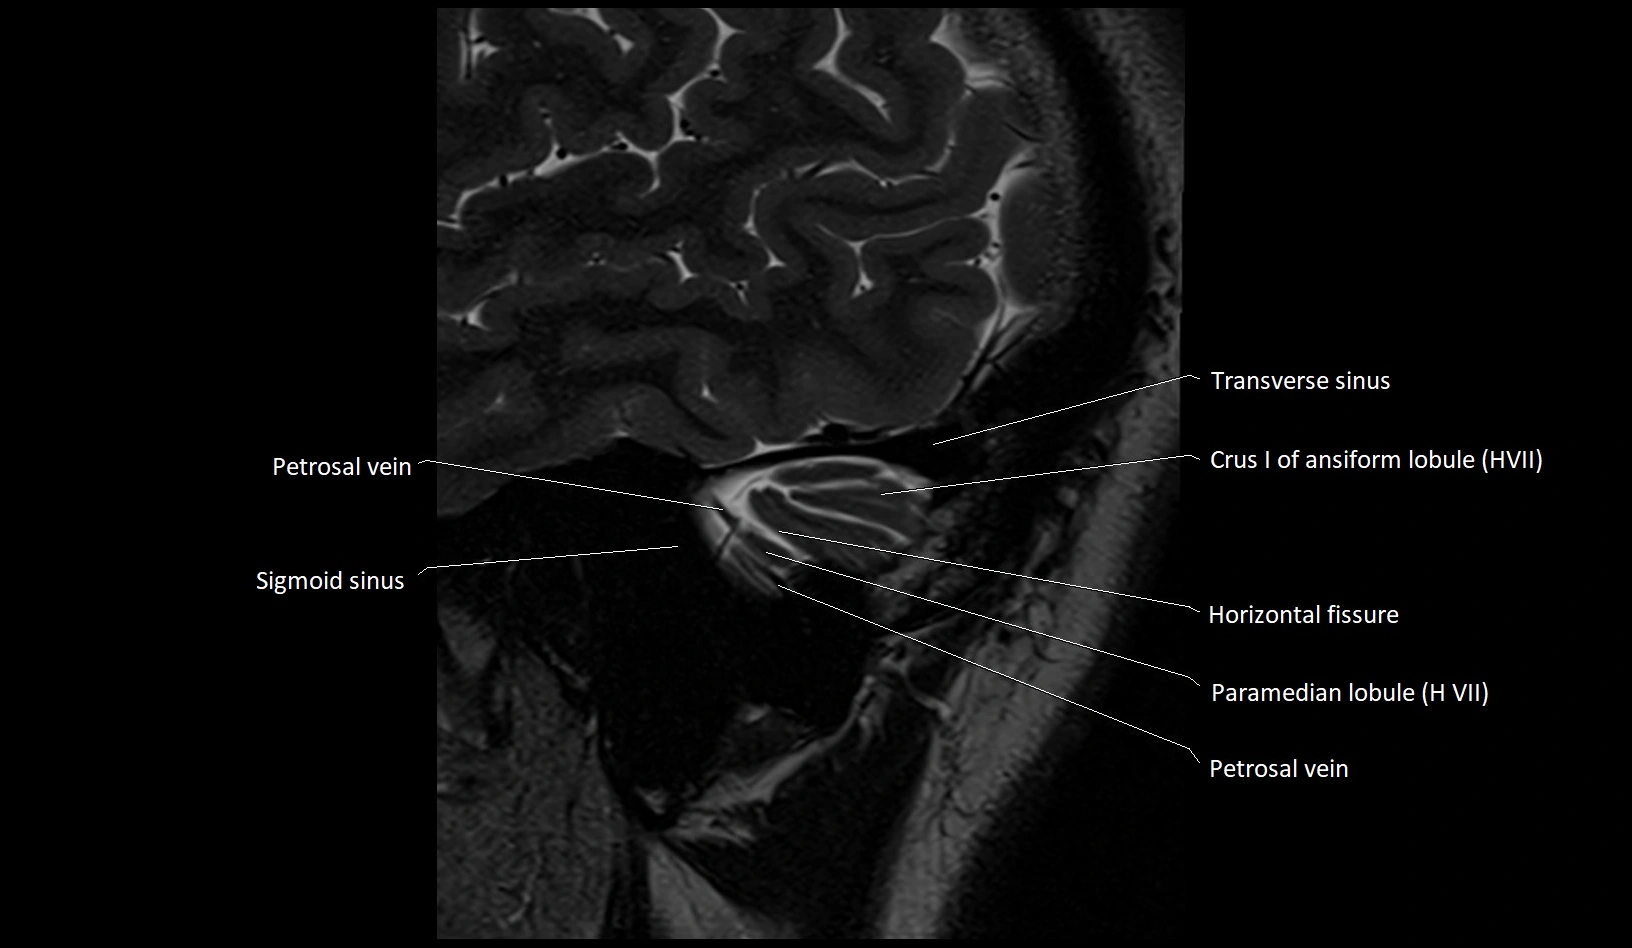

- Crus I of ansiform lobule of cerebellum

- Crus II of ansiform lobule of cerebellum

- Horizontal fissure (cerebellum)

- Paramedian lobule (HVII) of cerebellum

- Petrosal vein

- Sigmoid sinus

- Transverse sinus